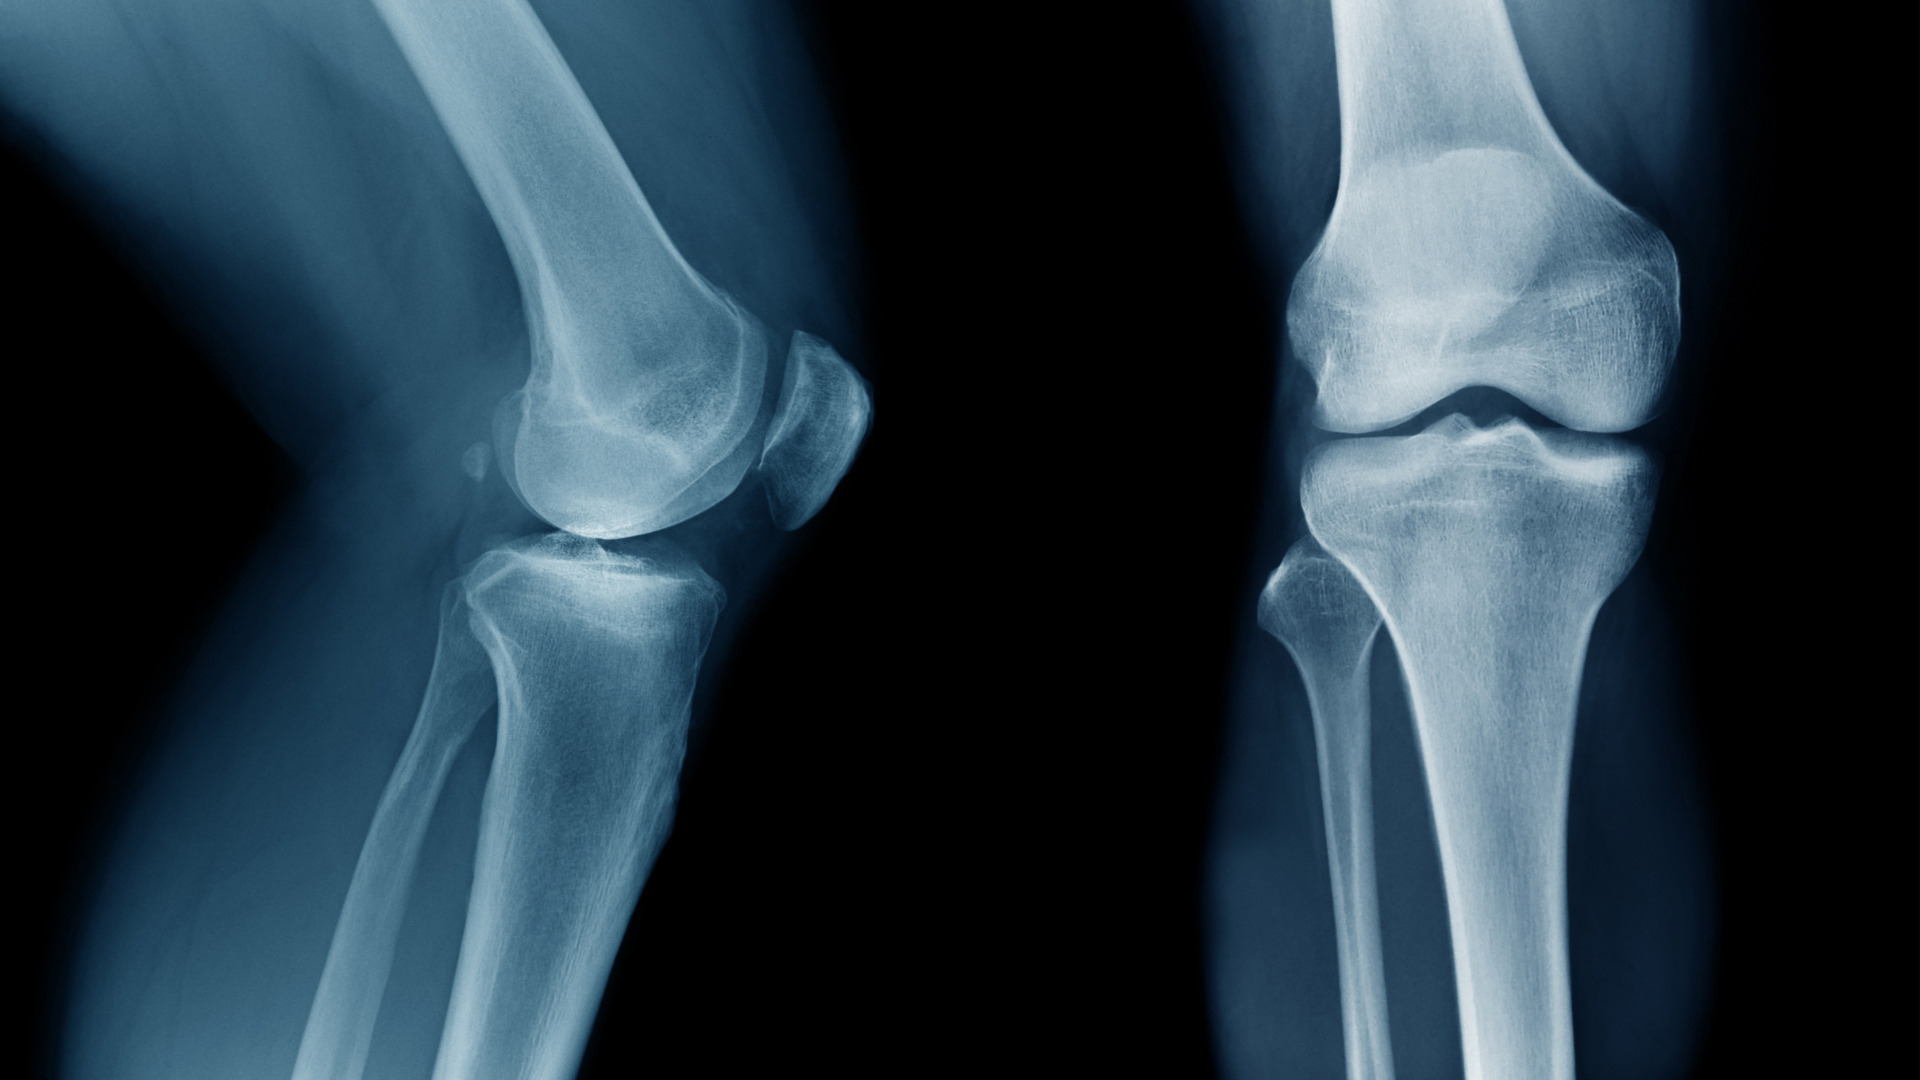

Việc phân biệt chính xác cần chẩn đoán hình ảnh (X-quang), do đó không nên chủ quan hoặc tự phán đoán tại nhà. Nhận biết sớm và đi khám chuyên khoa giúp ngăn ngừa các biến chứng như teo cơ, dính khớp, nhiễm trùng hoặc gãy lệch xương.

- X-quang: Phương pháp phổ biến, giúp xác định vị trí gãy, hướng gãy và mức độ di lệch.

- CT scan hoặc MRI: Dùng trong trường hợp gãy phức tạp, gãy kín hoặc nghi ngờ tổn thương kèm theo phần mềm, dây chằng, mạch máu.